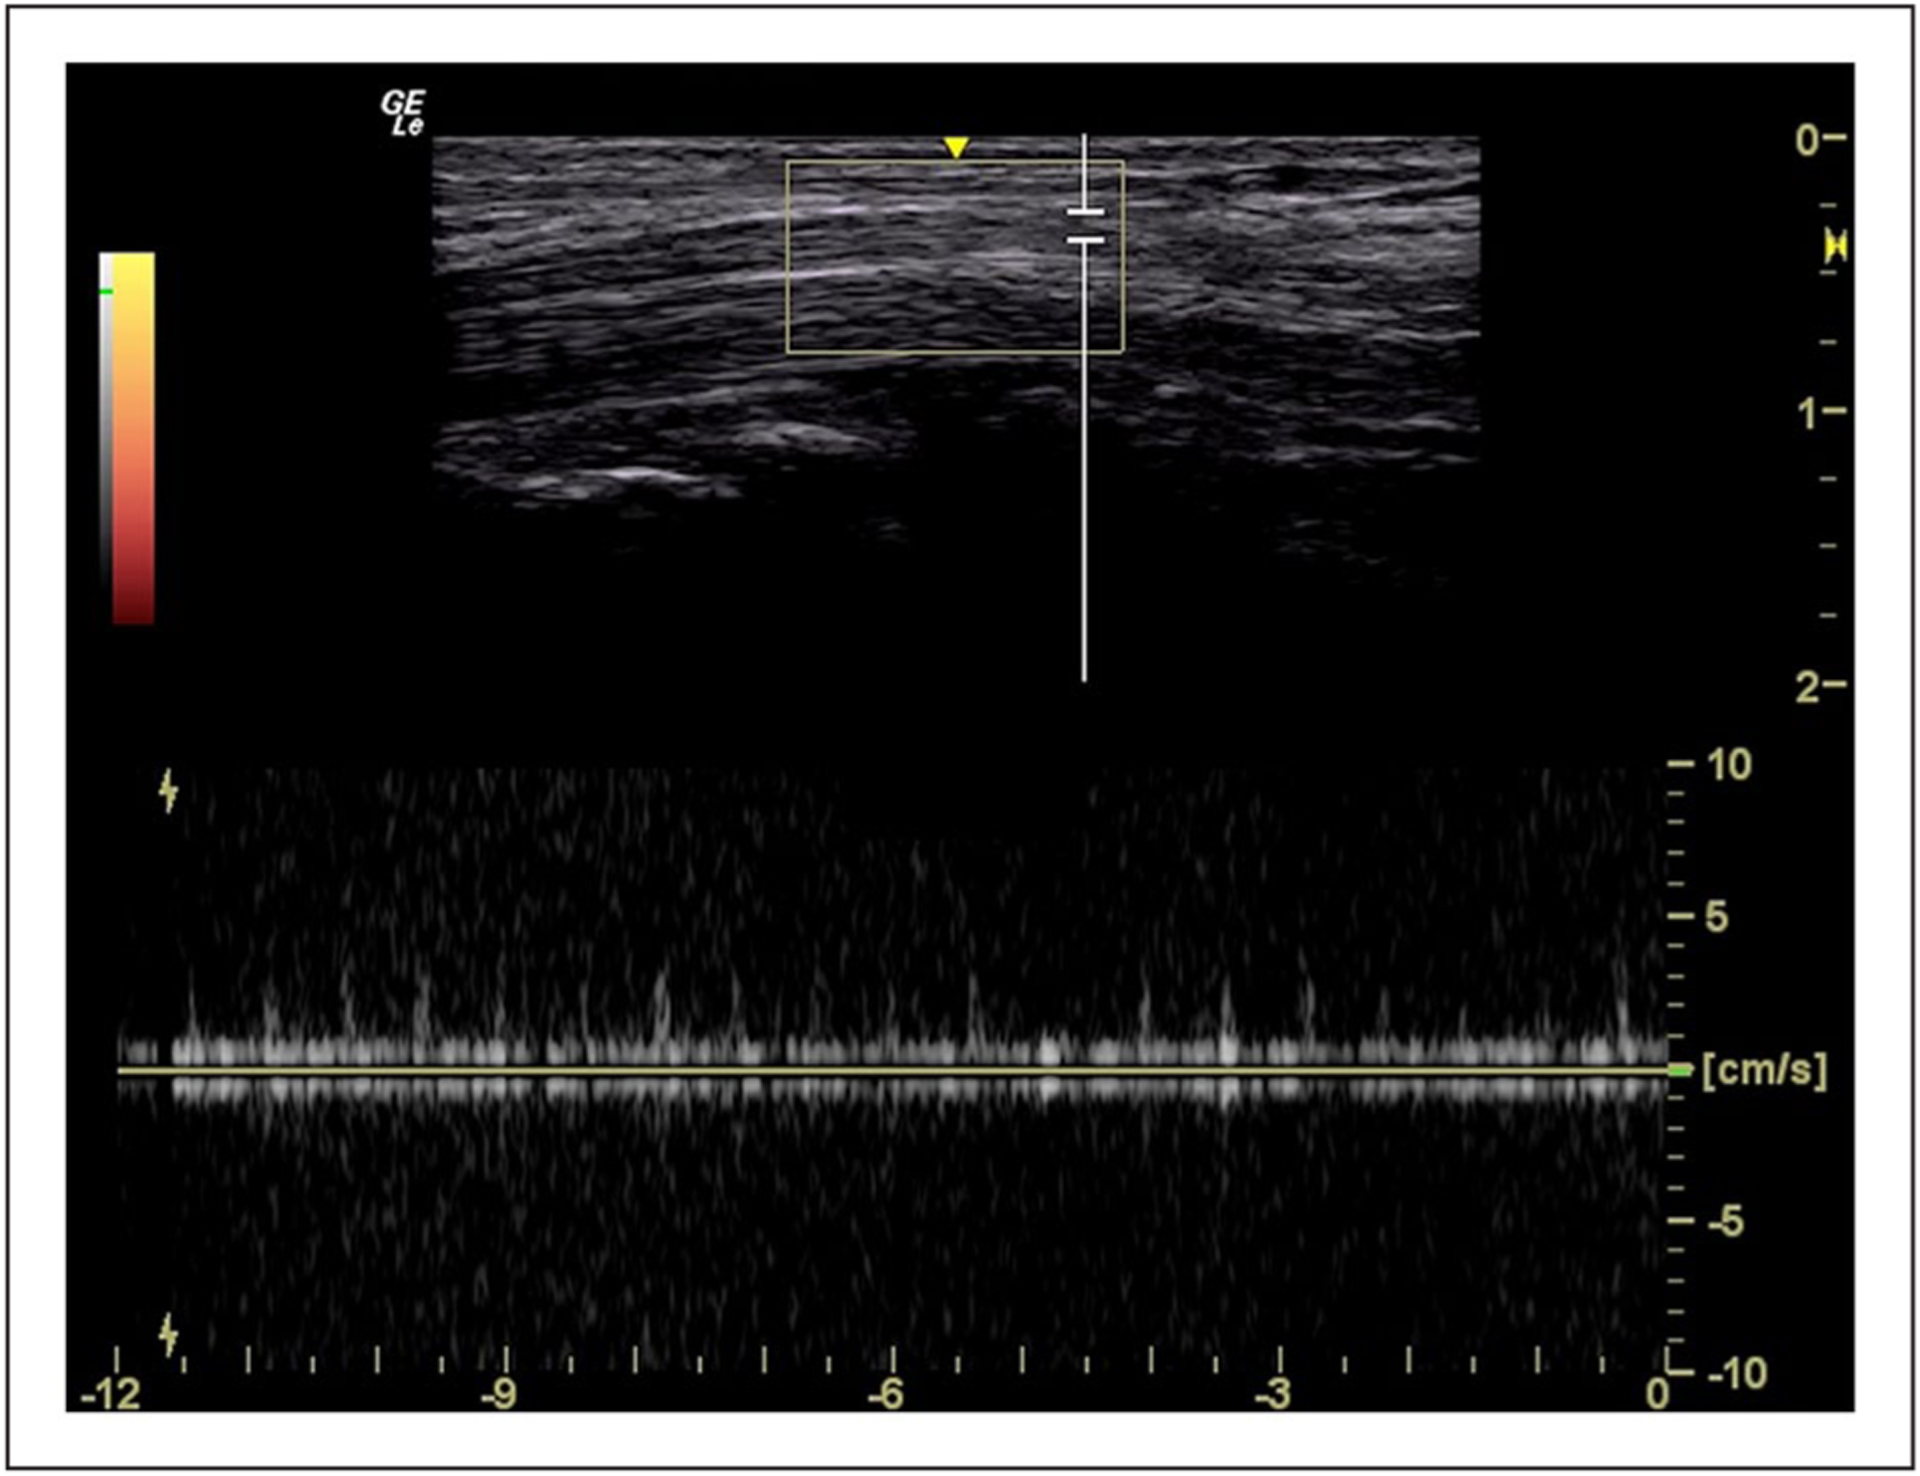

This study examined the implementation of a Doppler sonography imaging protocol to assess intraneural blood flow, within the median nerve, in healthy individuals.

A large percentage of missing evidence (11%–35%) across proximal, mid, and distal carpal tunnel locations. Only a quarter of cases with evidence of intraneural blood flow had the strongest evidence of a power Doppler video clip, of which only three-quarters were valid. The study identified potential areas for improving the imaging protocol to reduce missing data and improve data quality.

This study demonstrates the significance of a standardized imaging protocol to guide the sonographic acquisition of Doppler images and provides important insights into potential issues with data quality. The recommendations have the potential to help future studies assess intraneural blood flow in healthy populations in a more rigorous and reliable way. Incorporating the study’s recommendations into a standardized protocol, there is potential to enhance the diagnostic accuracy of carpal tunnel syndrome and improve diagnosis and treatment.